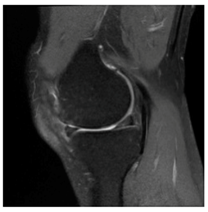

In this section, we present and analyze the results obtained with the proposed method, and compare it to methods proposed in similar works. The proposed watermarking system is implemented using MATLAB and executed on a Windows machine with the following characteristics: Intel R Core i5 processor, 4 GHz, 4 GB RAM, and Microsoft Windows 8 Professional operating system platform. In our experiments, we have used DICOM images of size 512 × 512 pixels as shown in Table 1.

Table 1.

Original images.